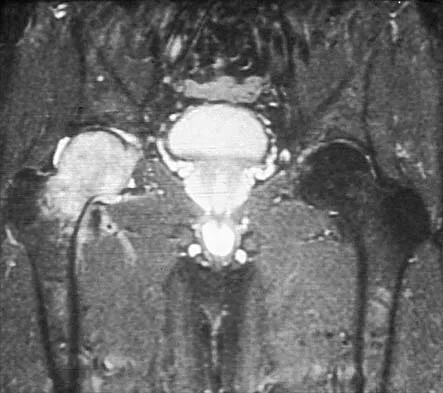

Question 39

Figure 26 shows the MRI scan of a 60-year-old man who has had groin pain for the past 2 months. The patient reports pain with ambulation, and examination reveals an antalgic gait. He denies any history of steroid or alcohol abuse. Plain radiographs are normal. Management should include